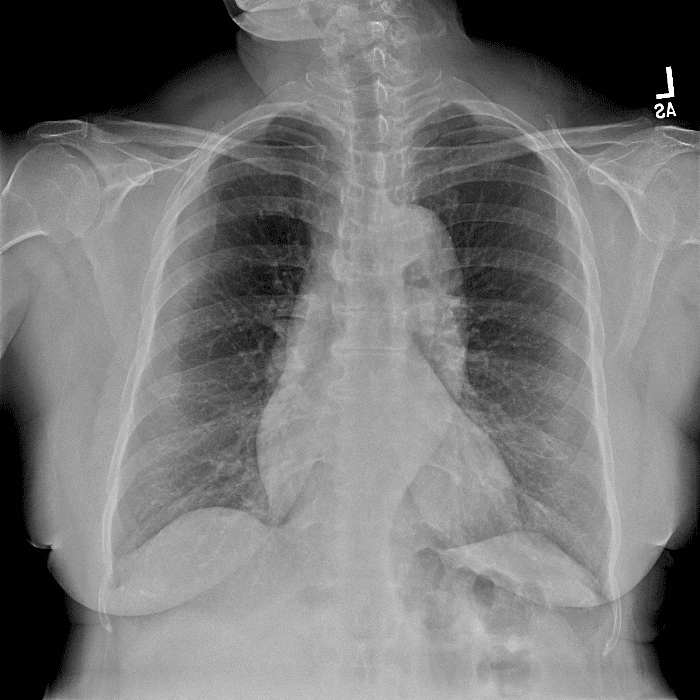

Practice Cases